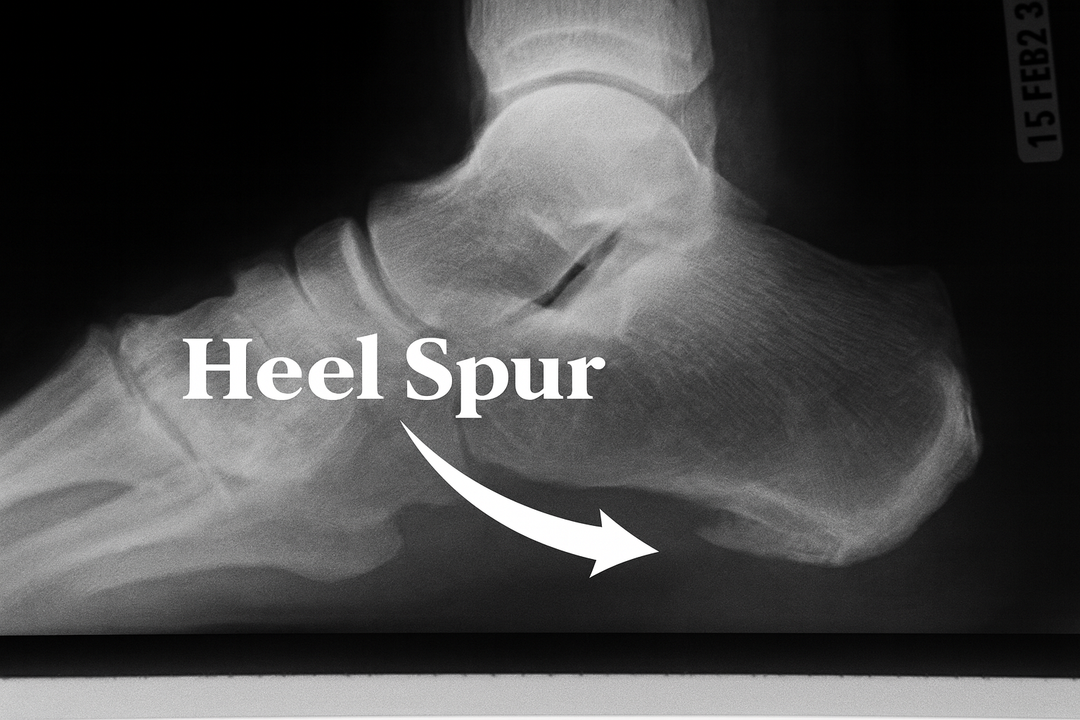

Heel Spurs – what they are and associated symptoms

Heel spur X-RayA heel spur is a bony growth on the heel bone (calcaneus). Heel spurs can cause sharp foot pain at the bottom or front of the heel bone. The pain in the heel usually subsides after a while, turning into a dull ache. The pain will often come back when getting up after sitting for a long period. The inflamed tissue around the spur causes pain and discomfort.

Continuous pulling of the fascia at the heel bone, eventually leads to the development of a bony growth on the heel, which is commonly called a Heel Spur.